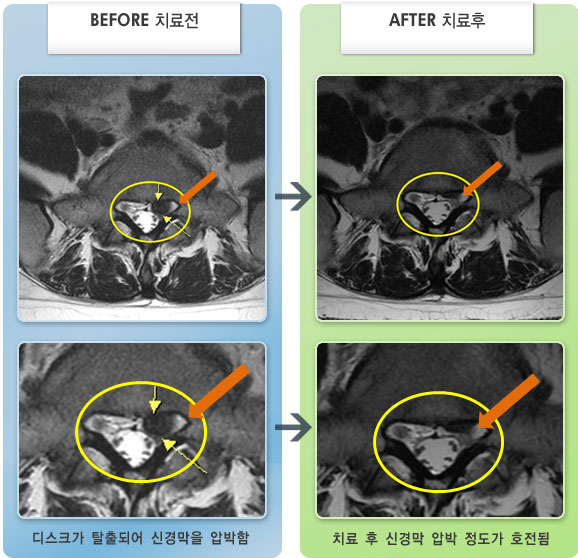

MRI 치료사례

허리 통증과 왼쪽 종아리 전기 통하는 느낌이 있었다.